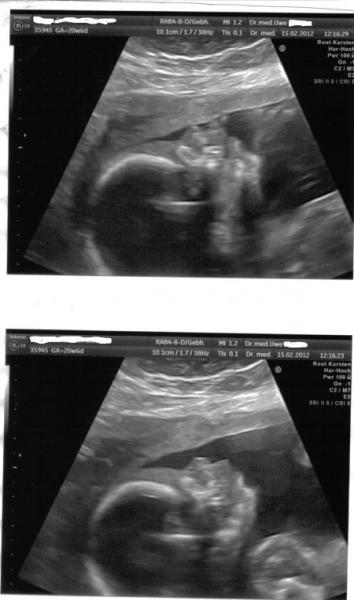

mit meinem baby ist alle top in ordnung. der schniepel der da ist der ist und bleibt auch also bekommen wir jetzt zu 100 % einen . Er hat am daum gelutscht und fruchtwasser getrunken. der arzt wollte 3 D machen aber Mister wollte sich nicht zeigen da war/bin ich ein wenig traurig . So jetzt mal zu den Maßen der Junge Mann ist 25 cm Groß und 345 gramm Schwer. Bilder folgen gleich. Ich bin aber super Glücklich das alles in Ordnung ist. Lg Susann die so Happy ist das Sie jetzt Sachen Paken tut und bis Montag zu Ihrer Mama nach Hamburg fährt mit Ihrer Tochter

Süßen Kerl hast du da Freut mich, dass alles ok ist und 25cm ist schon echt klasse... LG deine Keksi